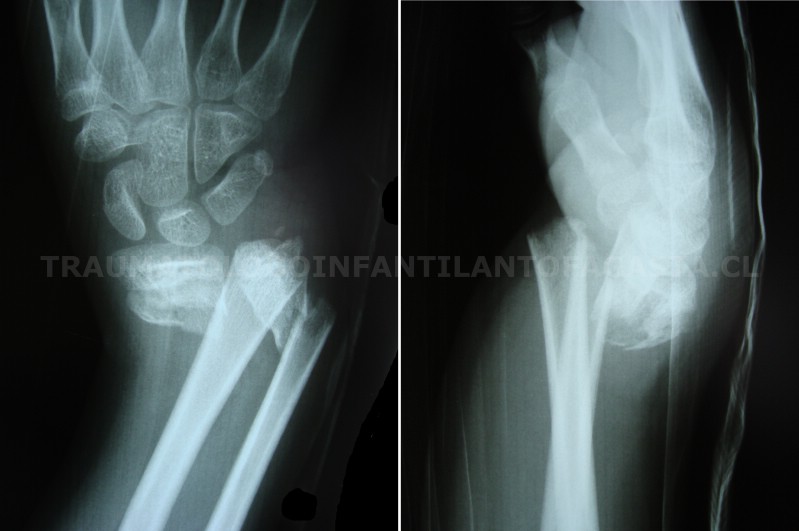

Fractura de muñeca